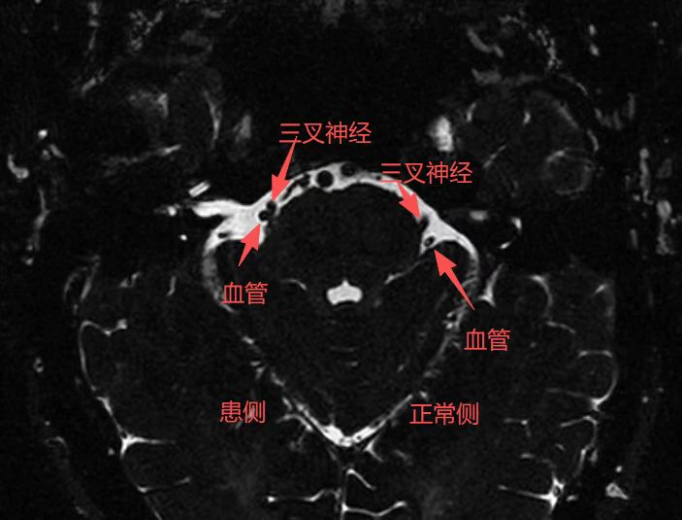

三叉神经痛,被称为“天下第一痛”,其症状表现为电击样、刀割样或撕裂样的剧烈面部疼痛,严重影响了患者的生活质量。针对李先生复杂的病情,南郊医院在崔海银院长等院领导,以及郭晓宾主任、陈安平大夫带领的脑科团队,组织了多学科会诊。通过结合患者疼痛的发作特点、频率变化及既往用药史,最终明确其病因为血管压迫三叉神经根部,并决定为其实施“三叉神经微血管减压术”。

手术在全身麻醉下开展,显微镜下,团队精准分离压迫神经的责任血管,植入特制垫片隔离,从根源解除异常压迫。手术过程顺利,术后李先生安返病房。